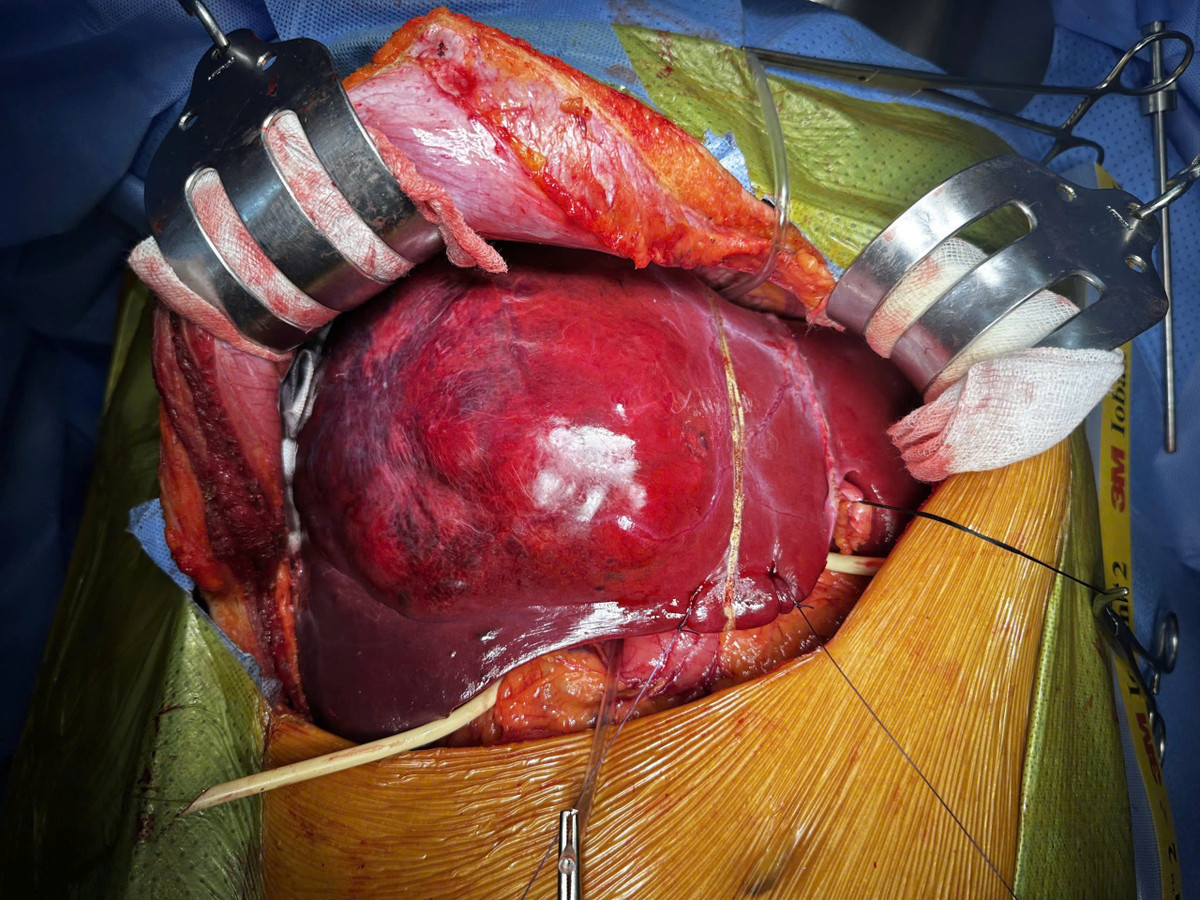

Ở giai đoạn hai, ê kíp phẫu thuật đã thực hiện cắt bỏ toàn bộ gan phải mang khối u, với khối lượng hơn 1,5 kg. Ca mổ thành công, bệnh nhân hồi phục tốt và không gặp biến chứng suy gan do thiếu hụt thể tích gan chức năng.

Gan với khối u gan phải khổng lồ và sau khi cắt bỏ gan phải - Ảnh BVCC